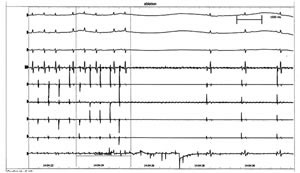

术前心电图 长R-P间期心动过速。P波窄而低幅,频率为150次/分,节律规整。心室律不规则,2~3∶1室房传导。心动过速时,Ⅰ导联P波低平、aVL导联P波正负双向、下壁导联(Ⅱ、Ⅲ、aVF)及V1导联P波负正双向,下壁导联P波负向程度大于V1导联(图1)。

图1 术前心动过速发作时心电图

图2 心动过速发作时腔内心电记录